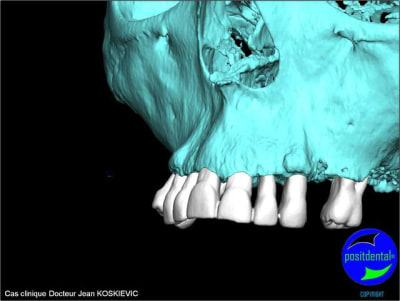

Montage esthétique ou wax-up 3D

rendu 3D maxillaire sup, pano et photo